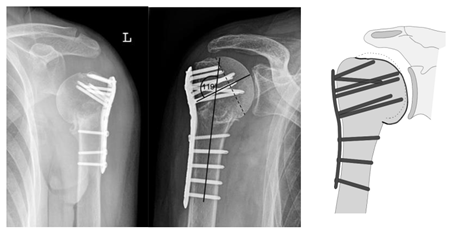

| Complication Type | Exemplary Images by X-rays or Pattern Images | Definition |

|---|---|---|

| 2b | ![]() | Complication Type 2b is limited to displacement of the greater tuberosity, lesser tuberosity, or both tuberosities. |

| 2c | ![]() | Type 2c is defined by a severe varus displacement (>20°) of the humeral head, which is associated with a screw cutout at the humeral head in parallel to Type 2a. In contrast to Type 2a, this varus displacement is characterized by an unstable osteosynthesis situation and progression. |